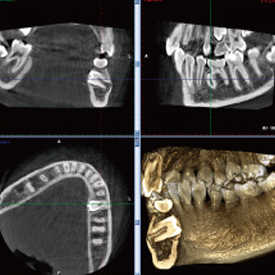

スマイルデンタルクリニックでは、歯科用CTを導入しているため、親知らずの形態、神経の位置を立体的に把握したうえで処置を行うことができます。

CTとはComputer Tomograghyの略で、日本語ではコンピューター断層撮影と訳されます。

これは、X線とコンピューターによって、歯や骨の位置や形態などを3D画像で立体的に撮影するための医療機器です。